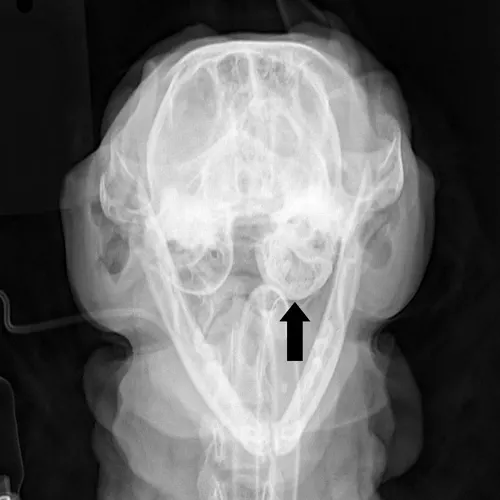

Feline inflammatory polyps are pedunculated benign fibrous masses that are infiltrated with inflammatory cells. Also known as nasopharyngeal, otopharyngeal, or middle ear polyps, these masses are most commonly found in cats younger than 2 years of age. The masses originate within the auditory tube or from the rostral aspect of the dorsolateral compartment of the tympanic bulla (Figure 1). Polyps may extend into the pharynx via the auditory tube, the external ear canal via rupture of the tympanic membrane, or both.

FIGURE 1 Ventral view of the skull demonstrating the two possible locations of inflammatory polyps: the external ear canal and nasopharynx. Courtesy Dr. Daniel A. Degner